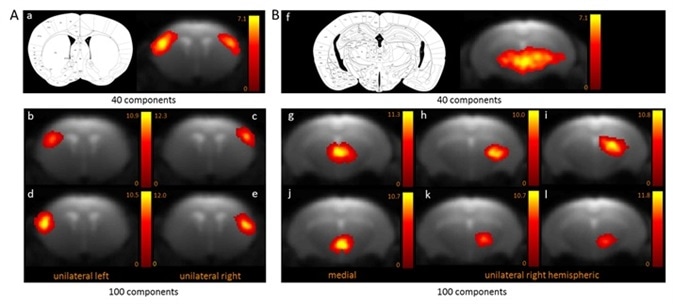

Two functional areas related to cortical (Figure 1A) and subcortical (Figure 1B) networks detected with 100-ICASSO and 40-ICASSO were comparatively presented. The cortical resting-state cluster, located at the primary somatosensory cortex (SSC) that is anatomically well-defined; secondary somatosensory cortex; and barrel field is all representative of the bi-hemispherical or bilateral connectivity pattern acquired with 40-ICASSO, as shown in Figure 1 A-a.

Refining the analysis with 100-ICASSO, as shown in Figures 1 A-b to e, led to the segregation of the functional areas of somatosensory cortex. Unilateral connectivity patterns were unraveled, which suggests that the SSC may have different low frequency variations of the BOLD signal in both hemispheres. Therefore, when 100-ICASSO is used, resting-state networks differentiated in single components from 40-ICASSO were divided into many functional circuits.

In addition to being relevant for cortical areas, this was also a common feature of subcortical regions. Shown in Figure 1B is the division of the thalamic networks, from a single component acquired with 40-ICASSO (Figures 1 B-f), into 6 functional clusters produced with 100-ICASSO.

Figure 1. BOLD resting-state fMRI based cortical (A) and thalamic (B) mouse brain functional connectivity clusters, comparatively revealed by 40- (a, f) and 100-ICASSO (b–e and g–l). All images represent spatial color-coded z-maps of the independent components. Image Credit: Bruker BioSpin Group